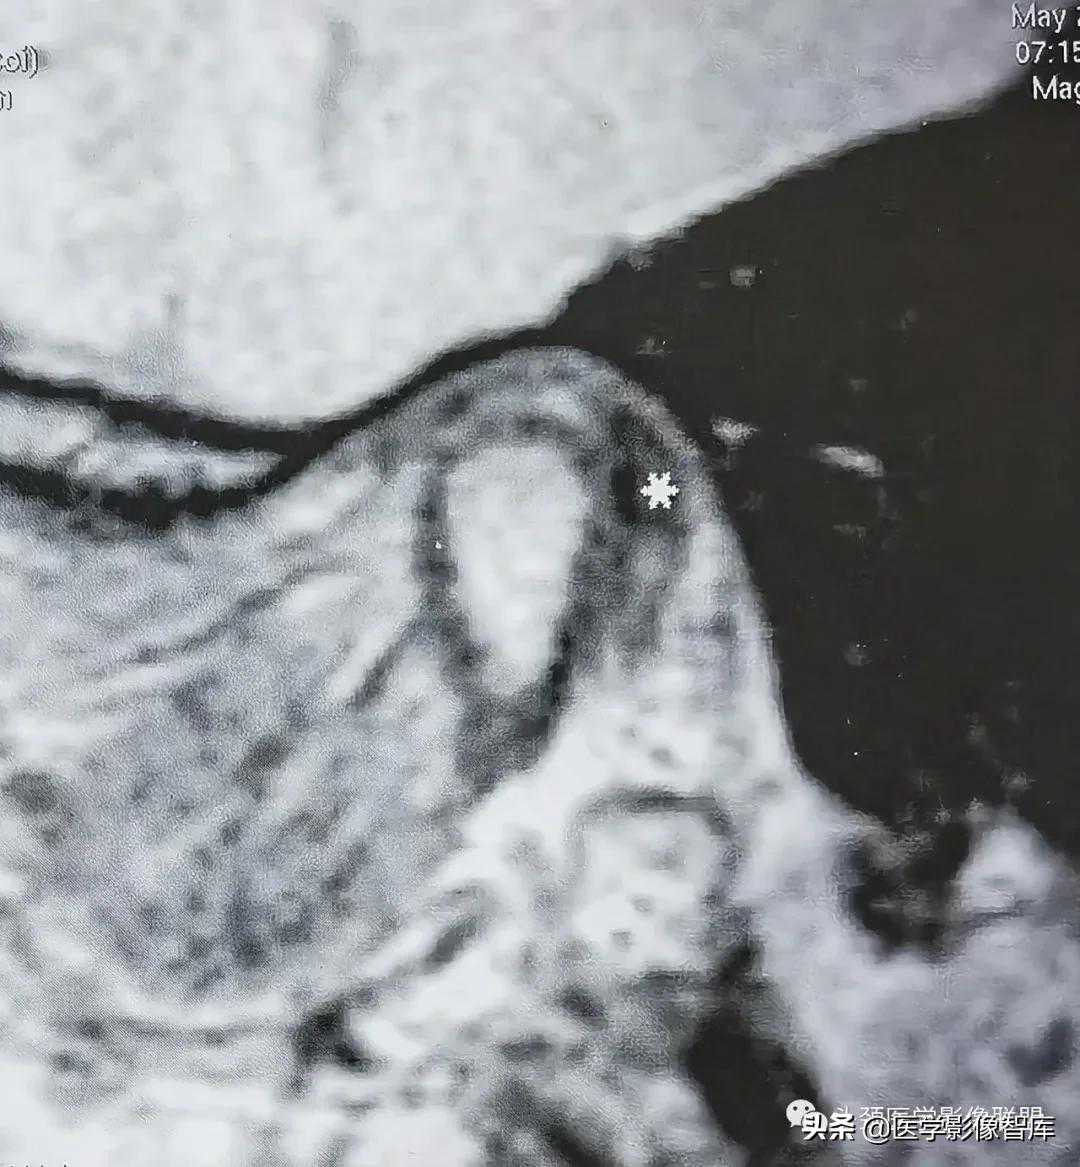

图5关节盘内移

冠状面闭口PDWI示关节盘(白星)位于下颌髁突内缘内侧。

在冠状面MRI上,如若发现关节盘明显位于髁突外缘的外方,则可作出为关节盘外侧移位的判断(图4B);若发现关节盘明显位于髁突内缘的内方,则可诊断为关节盘内侧移位(图5)。